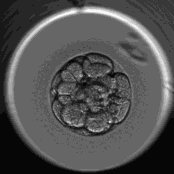

试管婴儿移植的胚胎分为第三天胚胎(卵裂胚)相当于受精后3-4天,第五天胚胎(囊胚)相当于受精后5-6天,胚胎移植后,移植的细胞团进入子宫腔内,并继续发育分裂成胚泡,准备植入,卵裂胚移植后着床的时间大概是5-7天,囊胚移植后着床的时间需要3-5天左右。